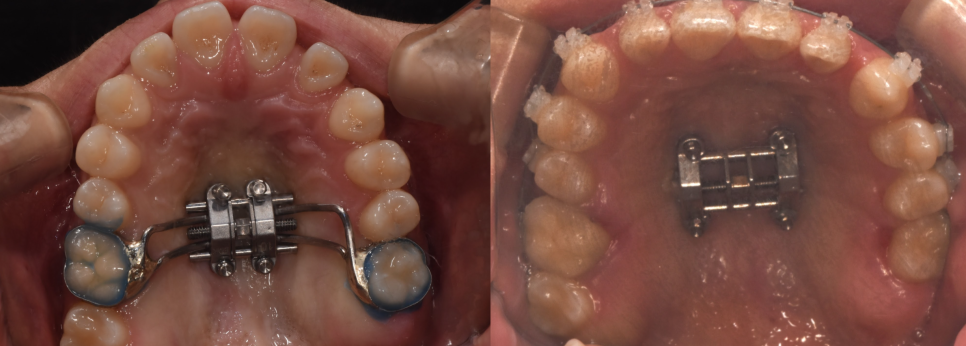

1단계: 상악 확장(위턱 넓히기)

가장 먼저 진행한 작업은 좁았던 위턱을 양옆으로 시원하게 넓혀주는 것이었습니다. 위턱이 확장되면서 아래턱과의 너비 균형이 맞기 시작합니다. 전후 사진을 보시면 좁았던 아치가 완만한 곡선을 그리며 넓어진 확실한 차이를 확인하실 수 있습니다.